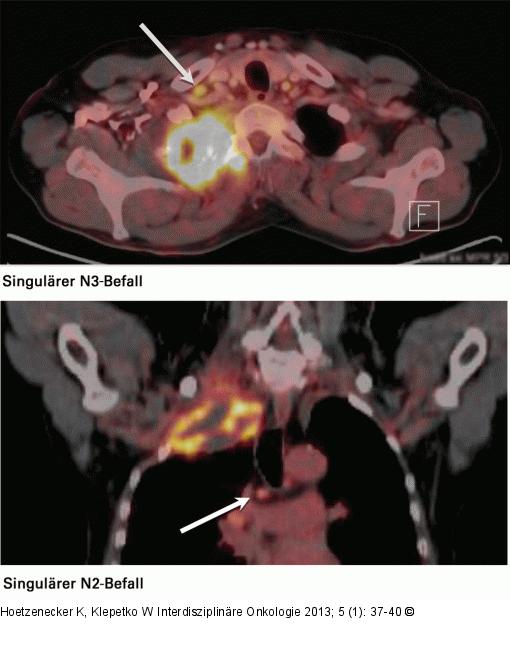

Abbildung 5: N3-Lymphknoten Diese beiden PET-CT-Bilder verdeutlichen die Wertigkeit eines befallenen lokoregionalen N3-Lymphknotens einerseits und eines subkarinalen Lymphknotens andererseits. |

Diese beiden PET-CT-Bilder verdeutlichen die Wertigkeit eines befallenen lokoregionalen N3-Lymphknotens einerseits und eines subkarinalen Lymphknotens andererseits. |